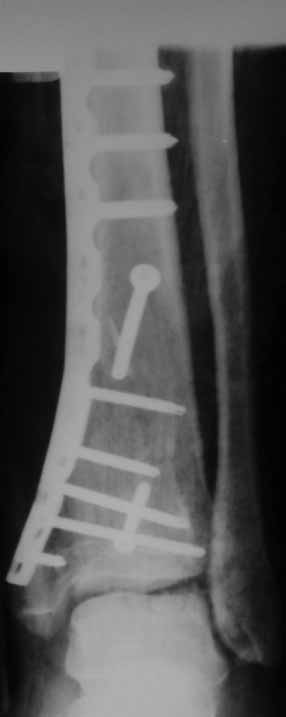

Извиняюсь пропал - оперировал "пилон". В форуме не хотел обсуждать финансовые возможности пациента. Потянул комбинированную пластину. Опыт общение с пластиной "крест" есть - не очень понравилось - слишком много места занимает, даже с учетом обрезаний лишнего. Сделал доступ огибающий медиальную лодыжку спереди. В переднем крае оказался достаточно крупный отломок - удалось зафиксировать винтом. Деффекта кости не оказалось.